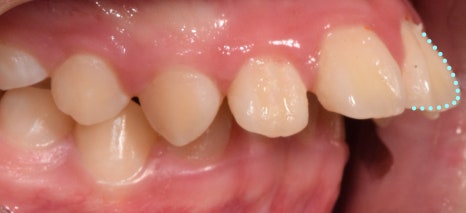

이번 케이스는

‘위턱이 많이 나온 상황’으로

측절치의 결손으로

위턱과 아래턱의 부조화가 나타났습니다.

이를 해결하려면,

위턱을 뒤로 밀어 넣어야 했기 때문에

헤드기어 를 활용해 교정을 진행하기로 했습니다.

턱이 뒤로 들어가면서

올바른 형태로 찾아갈 수 있었습니다.